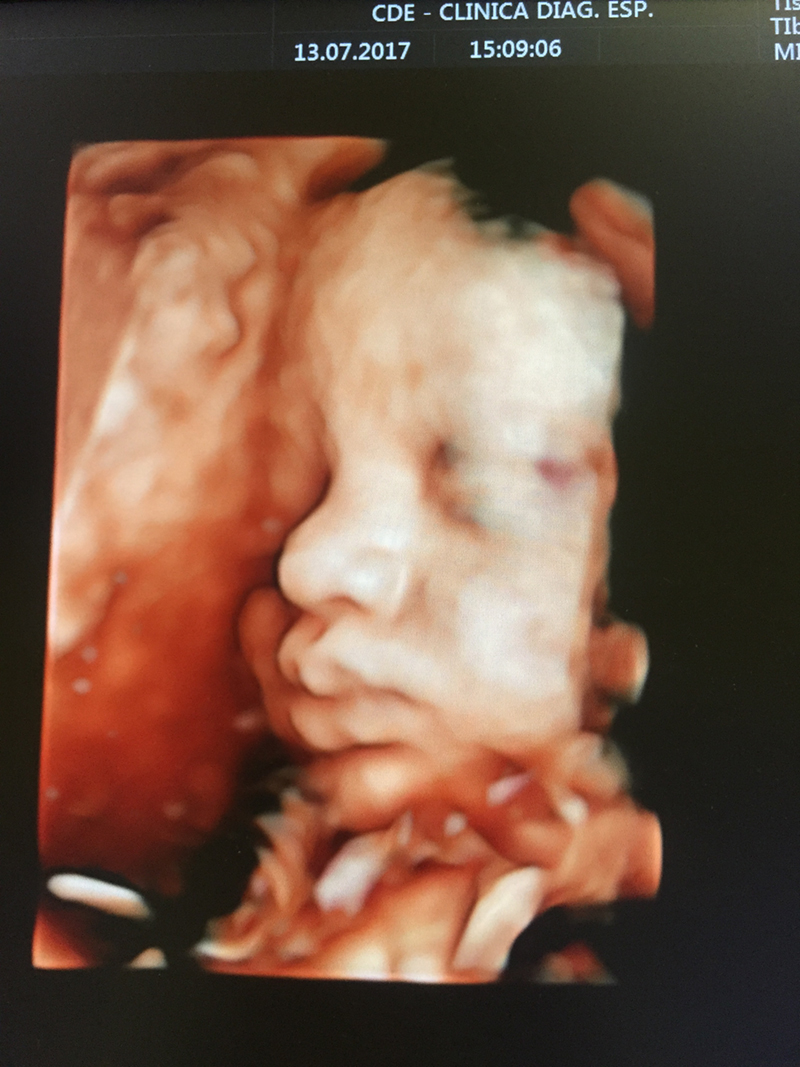

- Ultrassonografia Tridimensional 4-D;